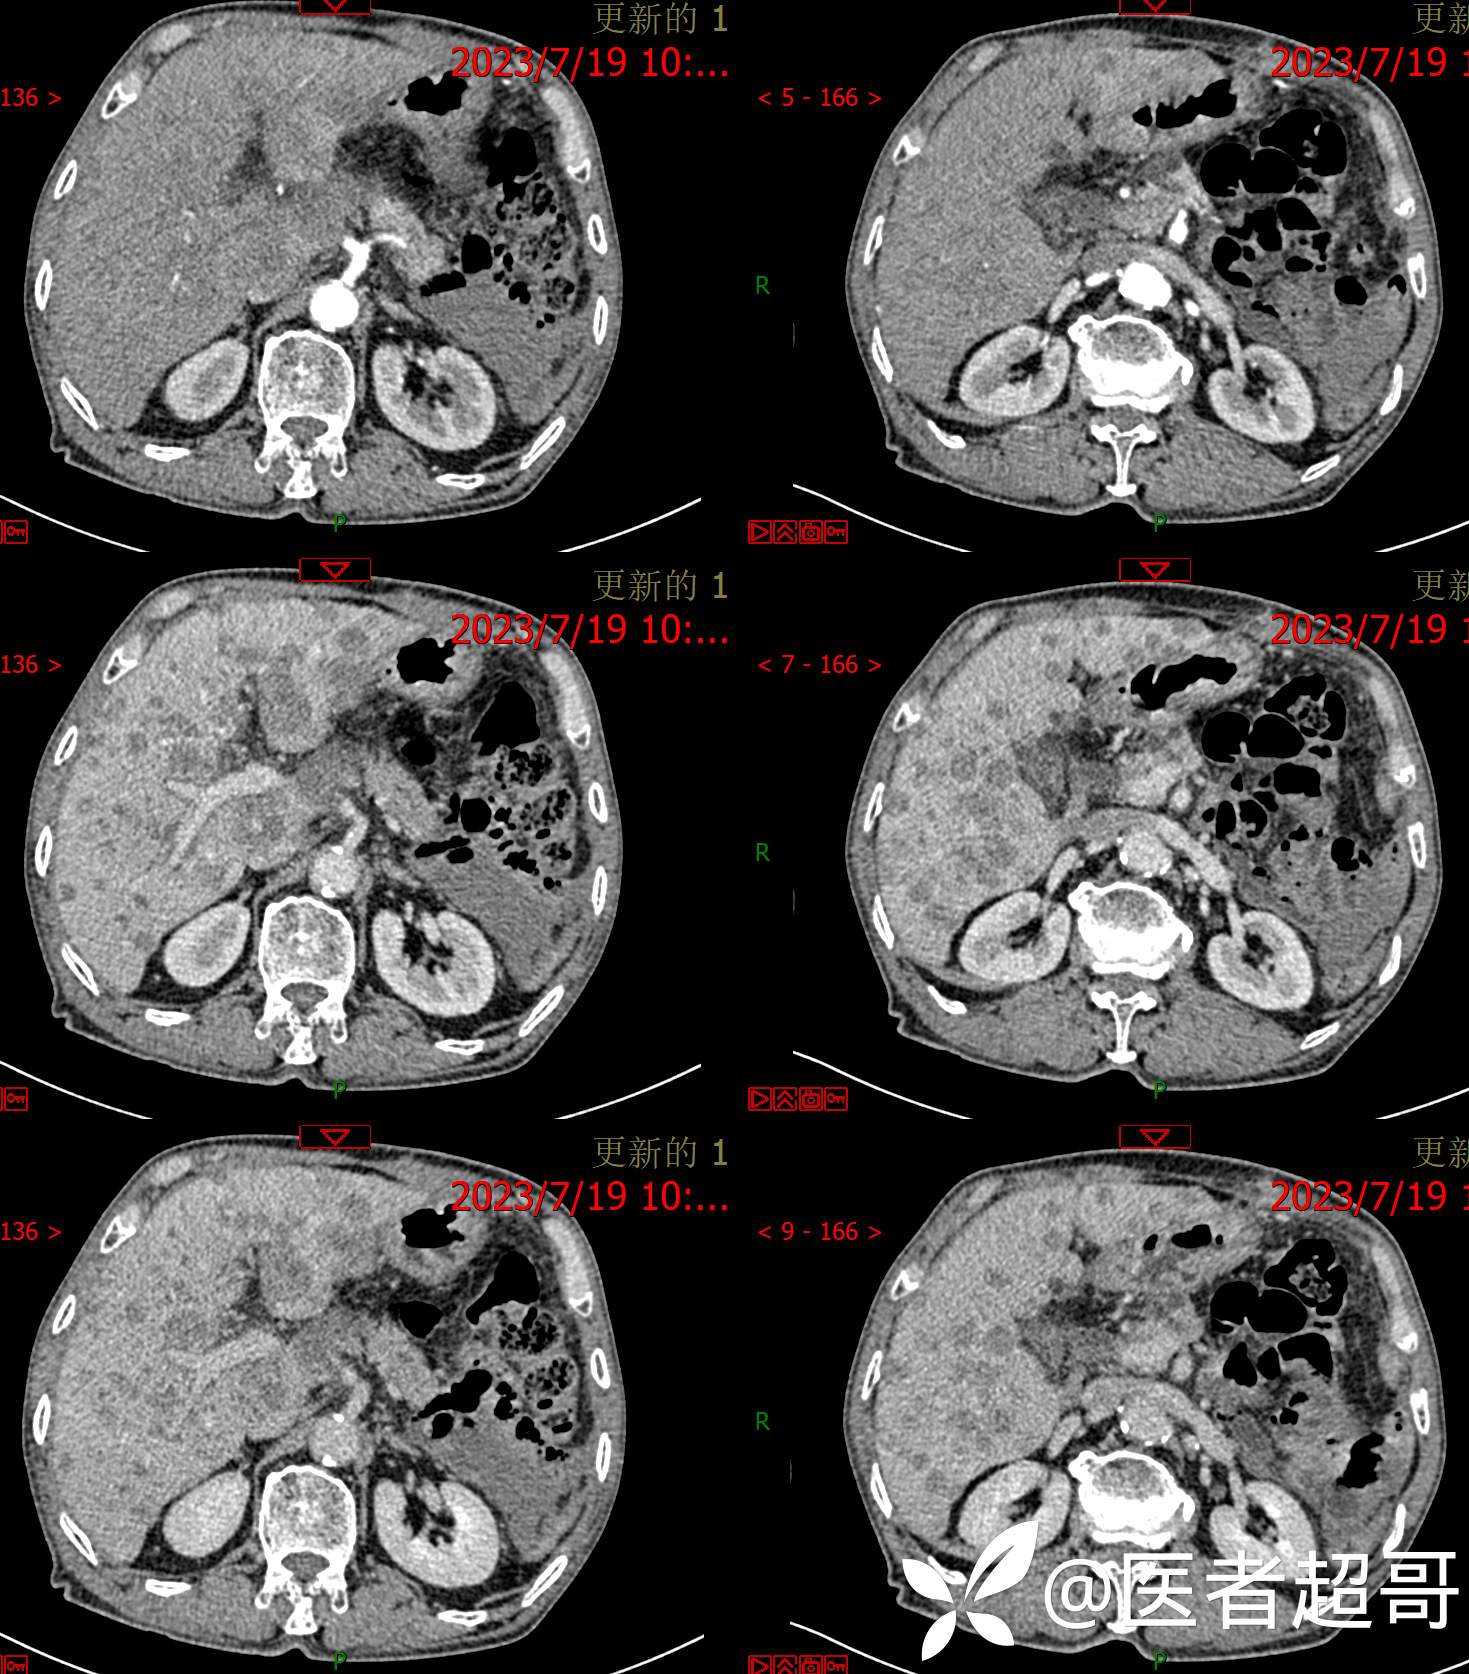

一波三折,术前确诊,术后肝脏广泛爆发,原因在何?让我们一探究竟!欢迎留言分析~~~

患者性别:男

患者年龄:76岁

主诉:左侧胸部疼痛不适5天就诊

简要病史:左侧胸部疼痛不适5天就诊,临床初步诊断“肋软骨炎”。

术后三个月复查CT、MRI表现:

转移性肝癌 (39)